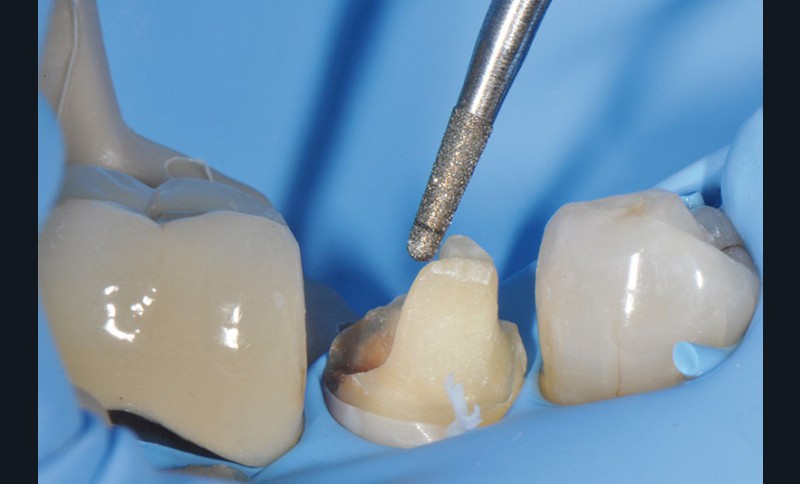

27, 28, 29. La couronne transitoire est pré-polie avec la roue spirale 3M™ Sof-lex™ beige puis polie avec la roue spirale diamantée 3M™ Sof-lex™ rose.